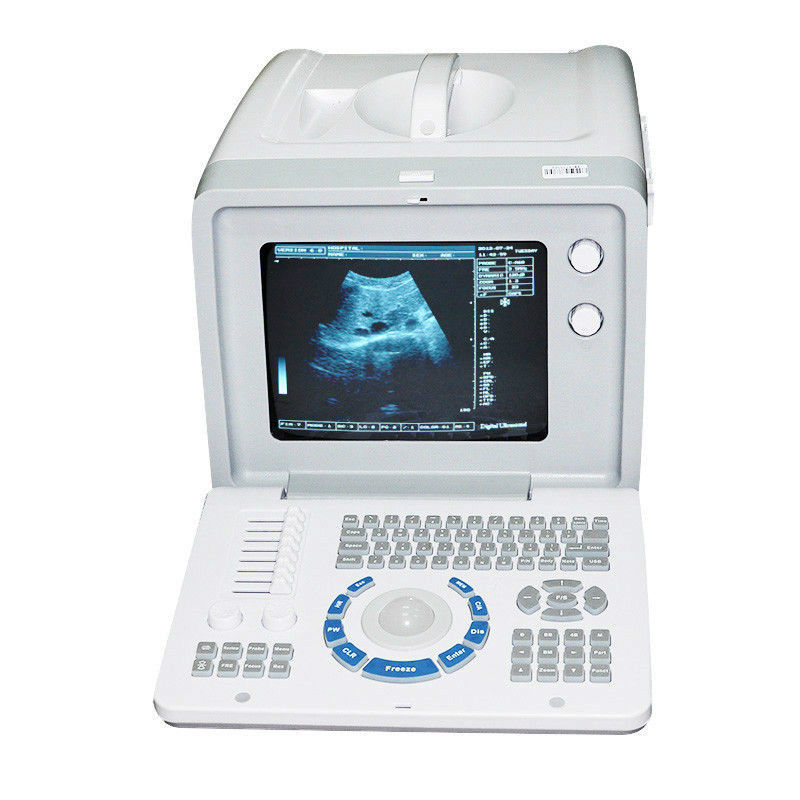

Comprehensive Diagnostic Capabilities

The Diagnostic Ultrasound Scanner provides a comprehensive solution for medical practitioners. It includes both convex and transvaginal probes, allowing for versatile imaging options. With the ability to create detailed images of various organs, this machine significantly improves diagnostic accuracy. Moreover, doctors can perform thorough examinations quickly and easily, so they can identify medical conditions early. As a result, patients receive timely care that can lead to better health outcomes.

Exceptional 3D Imaging Technology

This ultrasound scanner features cutting-edge 3D imaging technology, which enhances visualization during diagnostic procedures. The high-resolution images produced help healthcare professionals to analyze anatomical structures in greater detail. Additionally, the scanner’s user-friendly interface simplifies the imaging process, ensuring that practitioners can focus on patient care rather than complex setups. Therefore, this device aids in both efficiency and effectiveness in clinical settings.

Durability and Portability

Engineered for both durability and portability, the Diagnostic Ultrasound Scanner is ideal for various healthcare environments. Its robust design ensures reliable performance and minimal downtime, which is critical during busy medical shifts. Also, its lightweight nature makes it easy to transport between different departments or clinics. Because healthcare providers can adapt the use of this equipment in different situations, it enhances the overall capability of medical teams to deliver quality care.